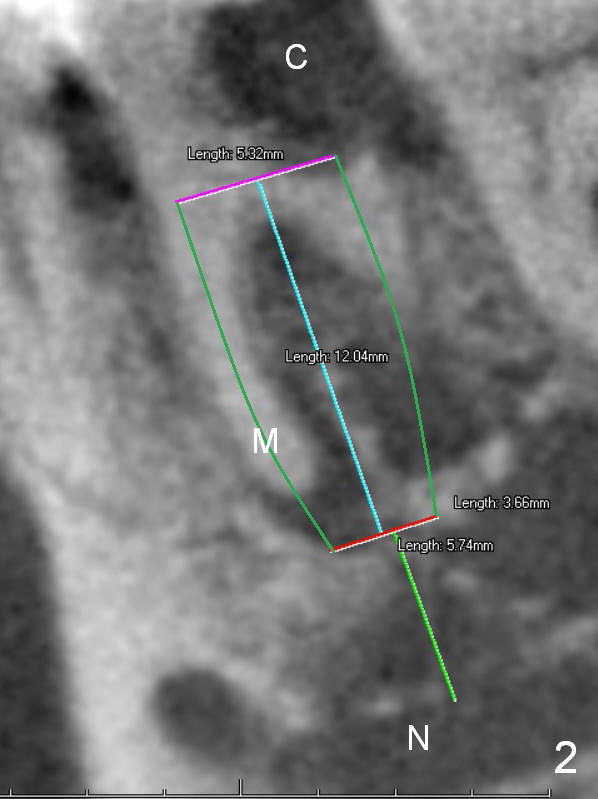

A 68-year-old lady (WQ) had CT taken 3 years ago (Fig.1-3), which show 3 roots (M: mesial; DB: distobuccal; DL: distolingual) of the lower right 1st molar and large caries (C). Recently the tooth fractures after root canal therapy (Fig.4-6).

Having 3 roots suggests a tripod septum. Surgical handpiece and elevators may be required, in addition to proximators. Cowhorn forceps should be helpful. The socket will be treated with Clindamycin, selected by time sequence.

An implant placed the tripod septum should be stable. The length of the initial osteotomy is 12 mm using 2 mm pilot drill. Take intraop PA as early as possible for trajectory and depth determination.